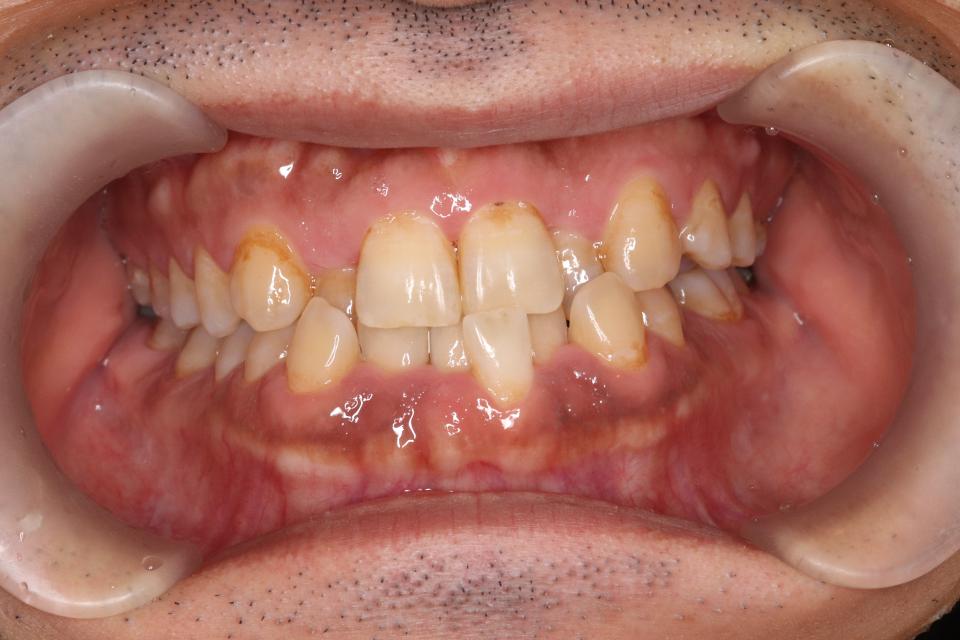

矯正治療前

30代男性です。

歯の凸凹が気になると来院されました。